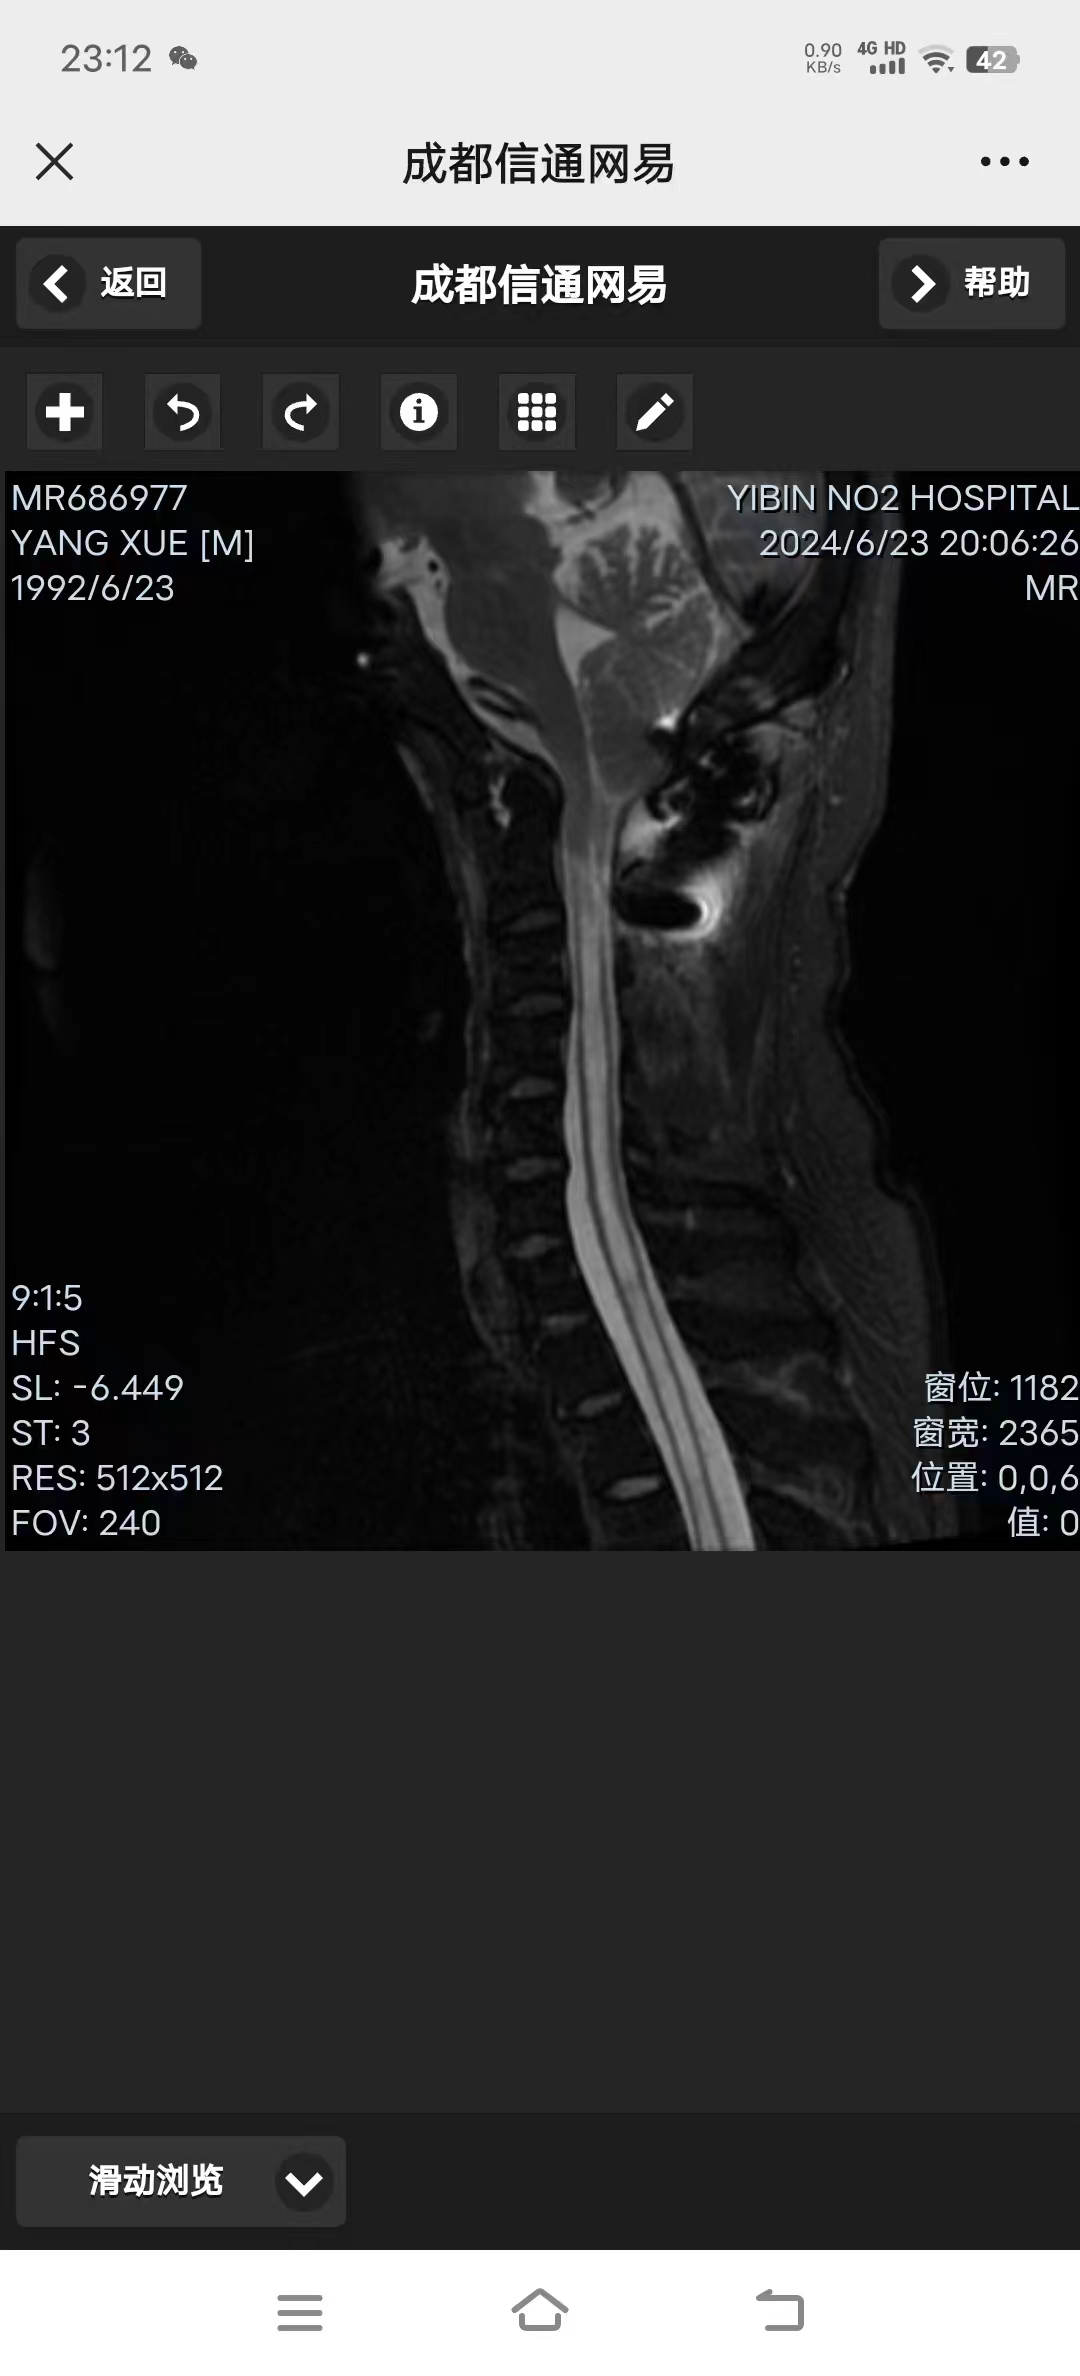

• 诊断:寰枢椎脱位、颅底凹陷、小脑下疝、脊髓空洞

• 影像: